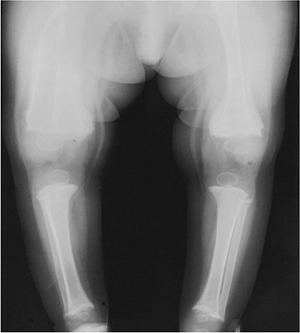

FIGURE 15-5

Melorheostosis. Standing views of the knees showing sclerosis and cortical thickening that crosses the joint into the soft tissues. The tibia also is involved. |